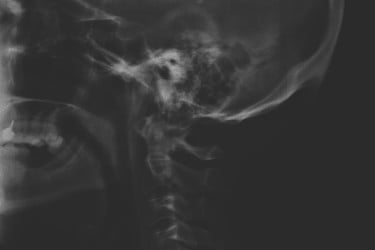

Sono un po’ perplesso sul fatto che questo osteofita, che accentua la parte posteriore del cranio, cioè l’osso occipite, si formi in una percentuale importante di persone per l’uso del cellulare. Mi sembra una forzatura questo legame, rispetto alle 2 o 3 ore al giorno che i ragazzi vivono a capo chino per studiare o a tutti gli impiegati che lavorano per anni alla scrivania. Senza voler criticare i colleghi, quotidianamente vedo radiografie per dolori alla colonna: spesso ci sono osteofiti, seppur non in quel punto dell’occipite, che sono legati al lavoro e alla sedentarietà.

Lo studio australiano si basa sulle lastre di 300 persone tra i 18 e i 30 anni. Le lastre arrivano dagli studi dei chiropratici australiani. Il campione è basso, ma non solo, il fatto che le lastre arrivino da studi di chiropratici è sintomo del fatto che questi soggetti si siano rivolti a uno specialista per un problema. Quindi sono persone che presumibilmente presentano dolori di qualche genere. Possibile che siano persone che presentano a priori quel tipo di formazione ossea. Solo un’analisi di lastre di un campione di popolazione che non si è rivolto al chiropratico può permetterci di fare confronti sensati. Ma lo studio quell’analisi e quel confronto non li fa.